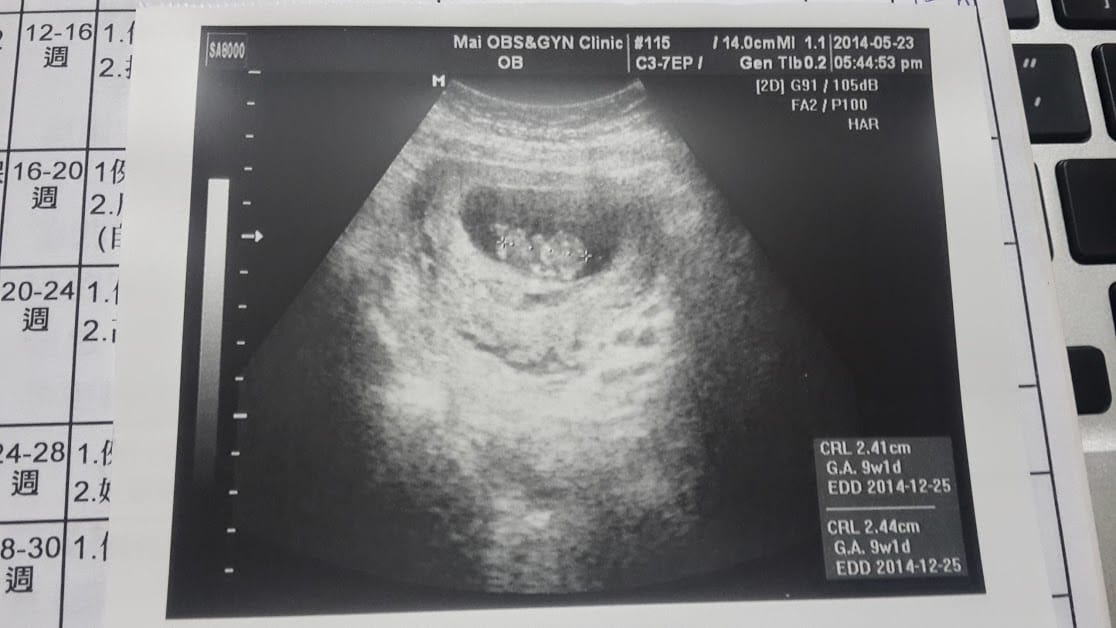

9W。第一次產檢

9W,畢竟還是好小好小一隻,雖然查資料時有孕吐表示有孕吐現象通常代表懷孕的結果還不錯,可是這次我還是很小心,

曾經有過一次空胚胎的的經驗,非常害怕聽不見胚胎心跳的那一剎那